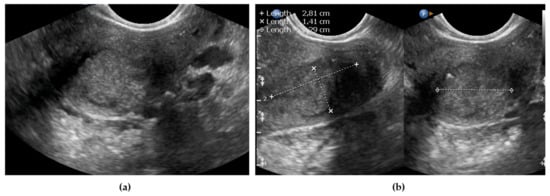

2.3.1. Endovaginal/Transrectal Ultrasonography